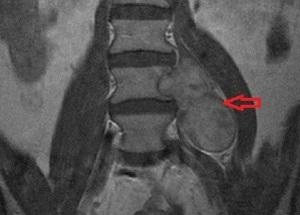

Невринома спинного мозга представляет собой доброкачественную опухоль, возникающую из нервных корешков позвоночника и формирующуюся из шванновских клеток.

Опухоль может расти на протяжении длительного времени, достигая размеров до 2,5 см. Наиболее подвержены поражению шейно-грудной отдел позвоночника, в то время как поясничный отдел затрагивается реже.